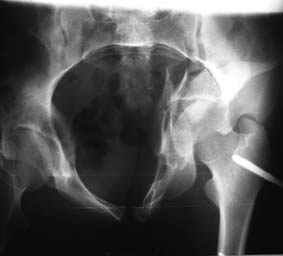

Это обзорные и косые снимки